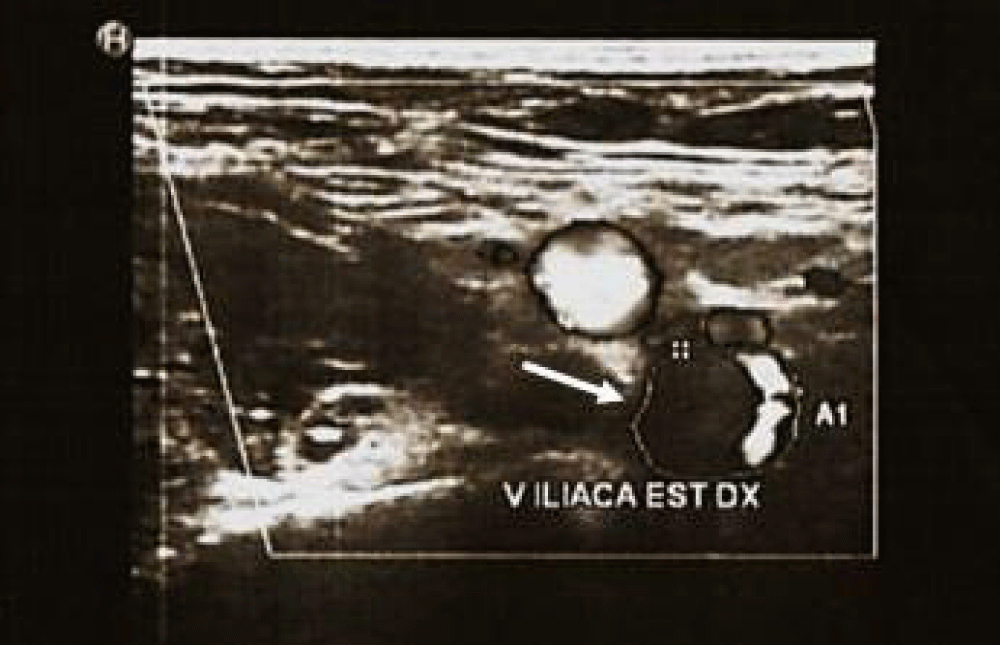

Moreover, a duplex ultrasound study of lower limb showed a thrombotic deposit with loss of color-doppler signals from the puncture site to the right external iliac vein (Figure 2). Echocardiography did not show signs of overload or dysfunction of the right ventricule or intracardiac thrombi.

Figure 2: Vascular ultrasound study with transversal view of the right external iliac vein, showing thrombotic deposit.